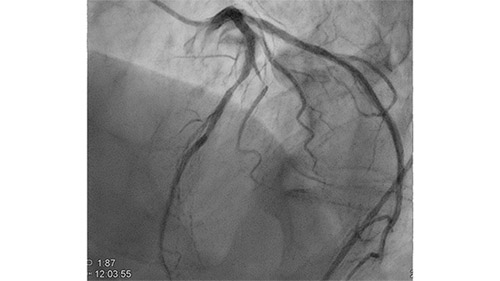

Dynamic Coronary Roadmap creates a dynamic, motion-compensated, real-time view of the coronary arteries. The software program overlays a highlighted coronary angiogram on a 2D fluoroscopic image, creating a colored map that adjusts automatically, providing continuous and exact visual feedback on positioning of wires and catheters.